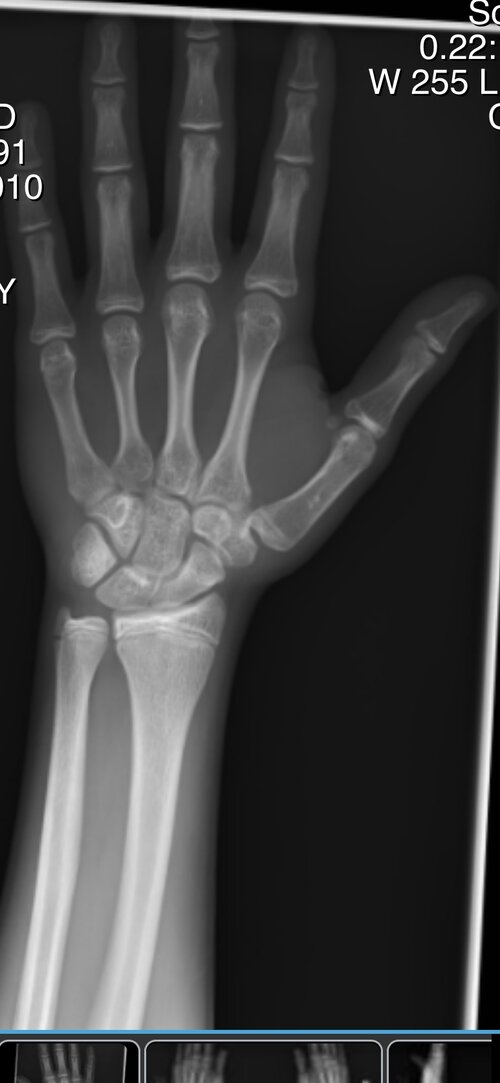

i’m 15 1/2, my plates are beginning to close, and i don’t want to be stuck in this fucking body forever, i’d do anything for aromasin or gh rn, is it truly over for me, if i stick to the gym ill just be a short stubby guy who no woman would want to approach. then again i could find a woman who truly loves me regardless of my height, but thats highly unlikely.:feelswhy: